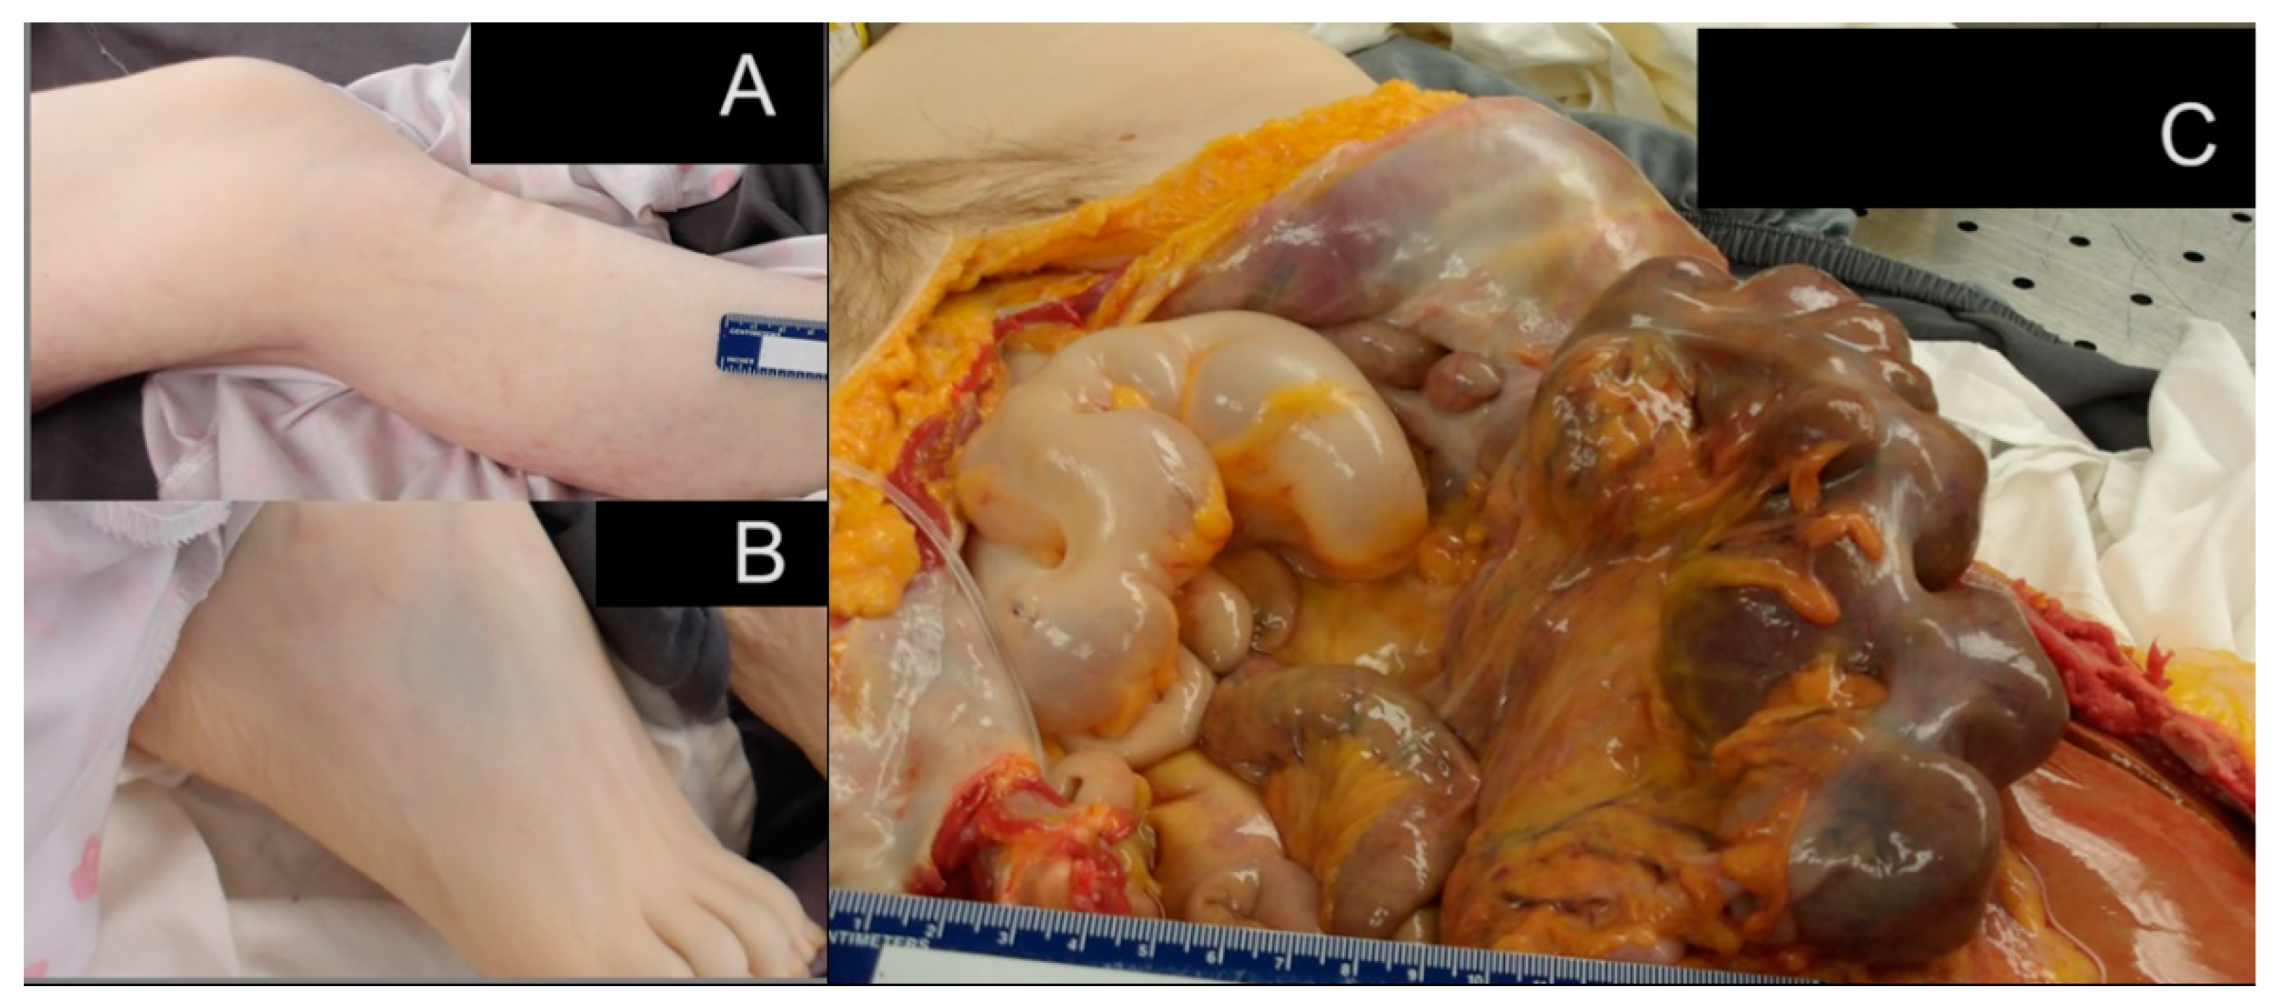

2.3.1. Gastrointestinal System Findings

2.3.4. Additional Significant Findings